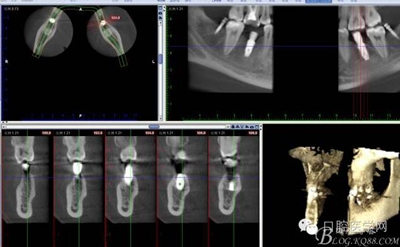

CT

因?yàn)榛颊咭蟀朐聝?nèi)完成,所以同期植入韓國(guó)豋騰4.5*10mm種植體